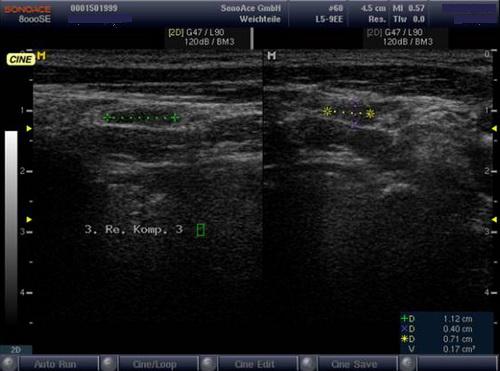

Sonografie: Eine mit einem Gesamtvolumen von 9,2 ml normal große Schilddrüse mit homogener echonormaler Struktur. Im re. Schilddrüsenlappen zentral ein inhomogener, echoarmer Knoten mit polyzyklischer Begrenzung, im Vergleich zur Voruntersuchung größenprogredient auf aktuell 2,8 ml Volumen, randbetont vaskularisiert.

Sonografie: Sonographisch 3 suspekte Lymphknoten cervical rechts.